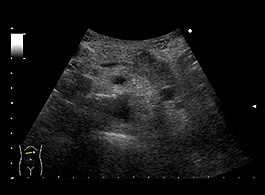

膵嚢胞は、膵臓上または膵臓内にある液体のポケットです。症状がほとんどないため、診断が難しい場合があります。これらは、別の問題の画像検査 ( CT スキャンなど) を実施するときに偶然発見されることがよくあります。

膵嚢胞の可能性が心配な場合は、医師に相談してください。病歴の検査に加えて、CT スキャン、MRI スキャン、超音波内視鏡などのさまざまな検査を実行できます。

検査後、医師は細胞が癌性かどうかを判断するために体液のサンプルを採取することがあります。膵炎が進行している場合は、嚢胞が再発する可能性があることに注意することも重要です。